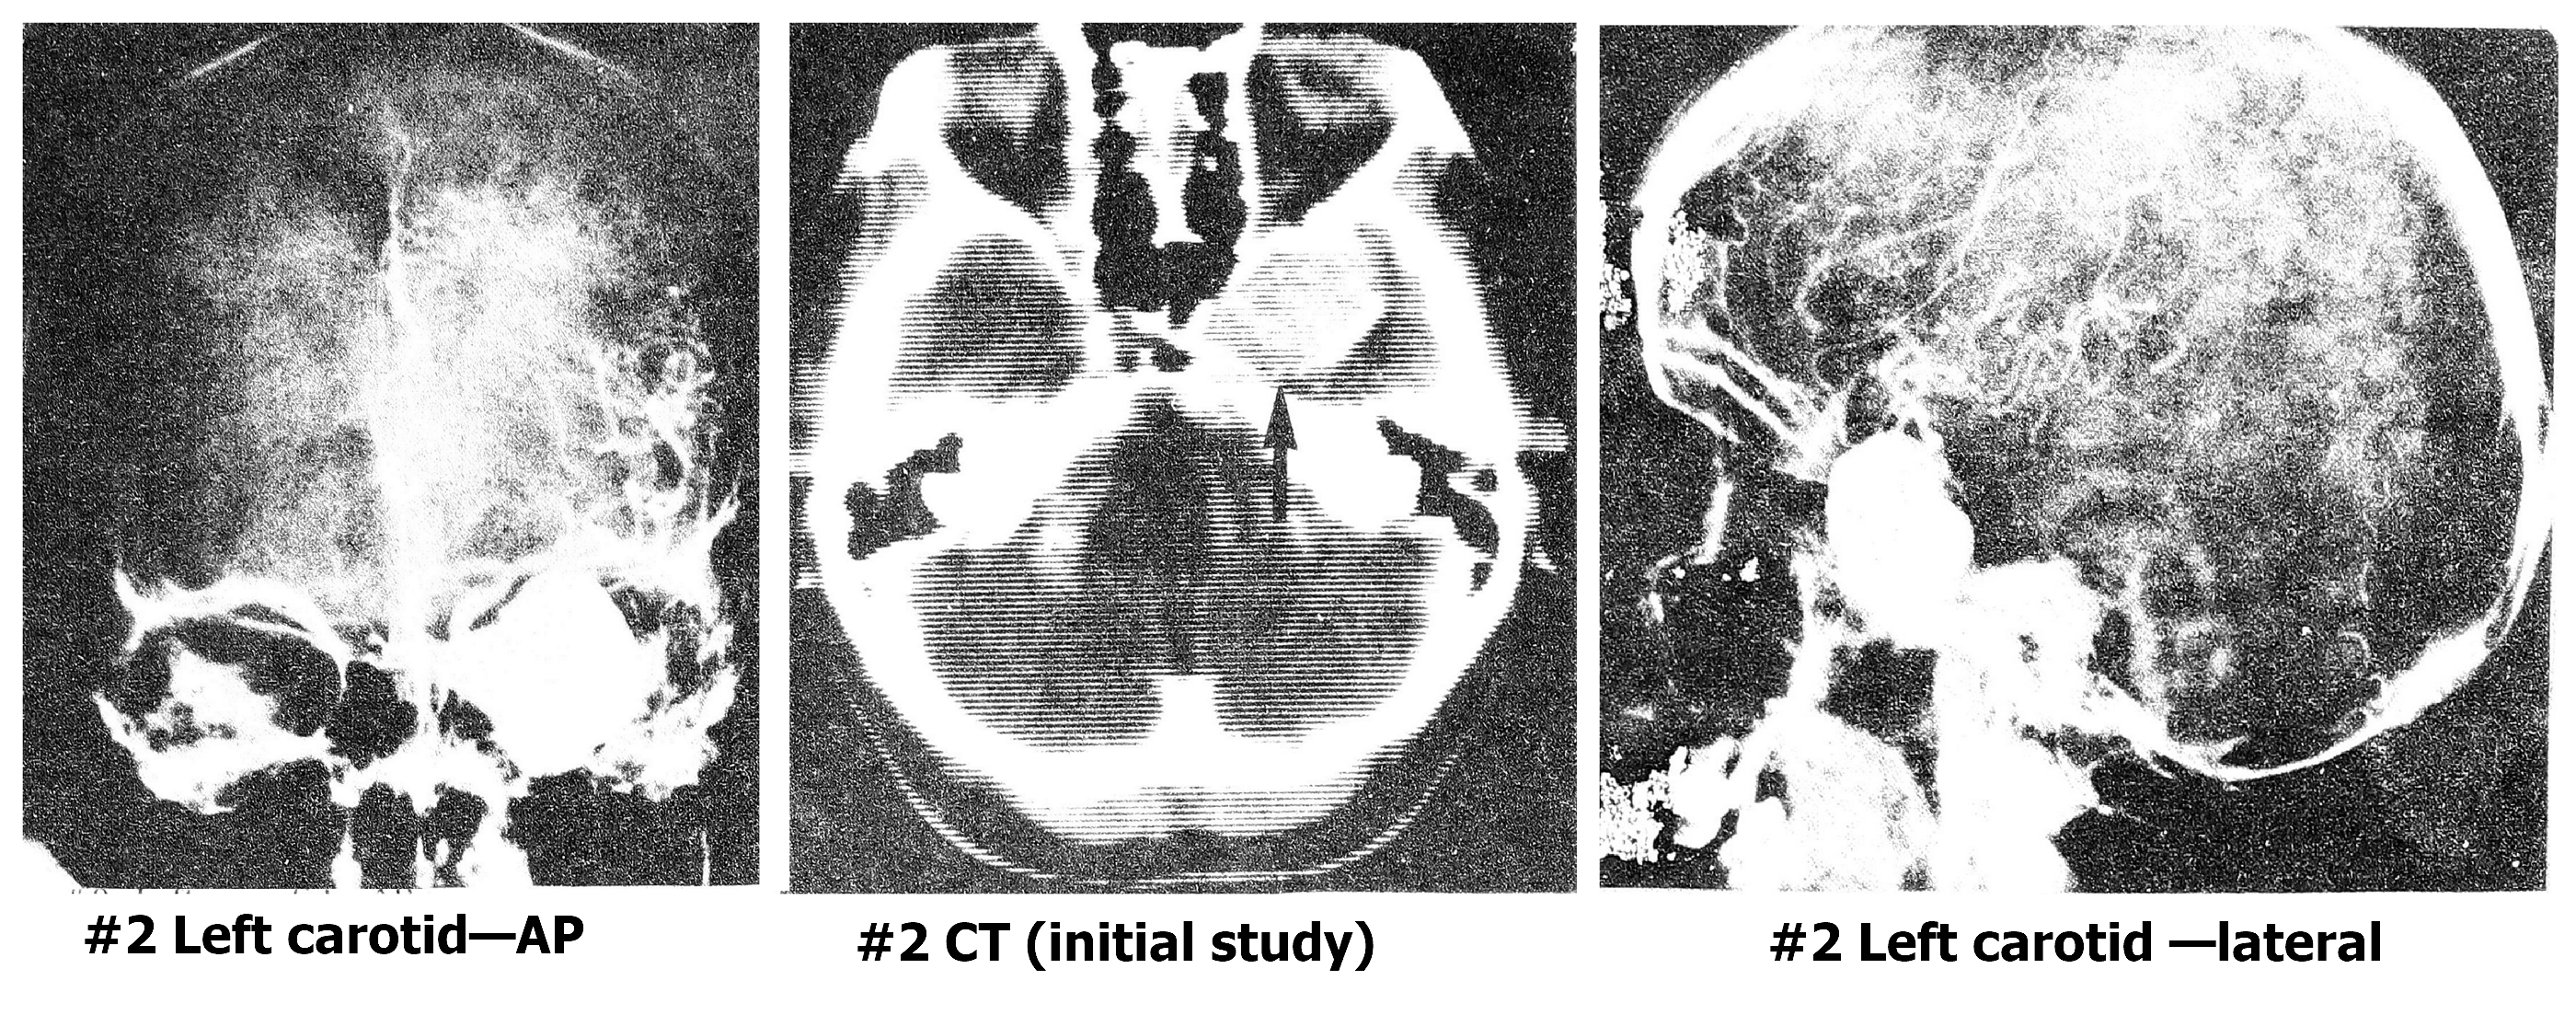

Рис. 2 А. Гигантская аневризма левой сонной артерии, по данным автографии и КТГ, до начала лечения (случай 2).

Рис. 2 Б. Тот же случай 9 лет спустя (по данным МРТ).